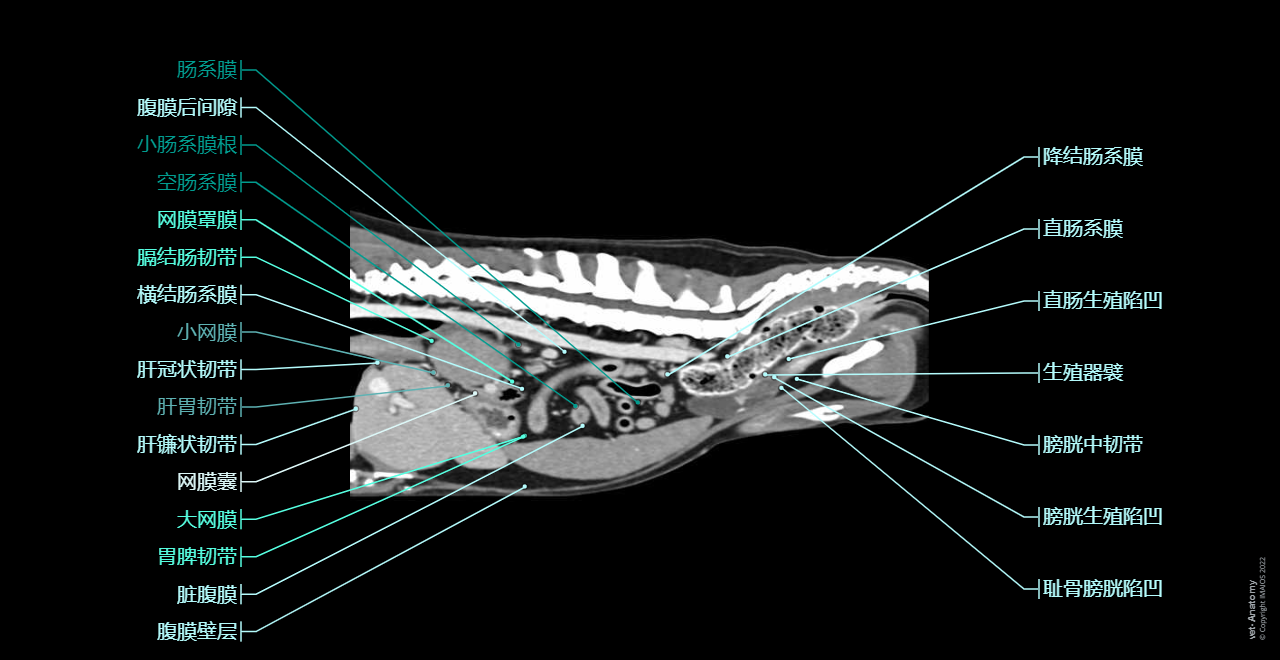

vet-Anatomy兽医图集的本模块是关于CT扫描的犬类腹部和骨盆。

CT图像来自一只健康的6岁阉割雄性犬。

在vet-Anatomy动物图集的此模块中,计算机断层扫描(CT)显示了标有解剖结构的犬科腹腔和骨盆横截面,并用3D图像显示犬科腹部。

CT图像存在3个平面方向(横向,矢状和背侧),并且使用两种对照方式(软组织/血管和骨骼)展现。本模块的末尾提供其他3D解剖图像,便于进一步了解犬科总体解剖结构,展示了骨骼、内脏(肝脏、脾脏、胰腺、消化道)、泌尿生殖系统、动脉、全身静脉系统(主要是尾腔静脉及其分支)、门静脉系统、肌肉和表面解剖的三维容积透视图。

毕业于欧洲兽医诊断影像学学会的Susanne AEB Boroffka博士(荷兰乌得勒支)对健康的6岁雄性阉割犬(拉布拉多猎犬)注射碘化造影剂并完成计算机断层扫描。

放射科医生(法国蒙彼利埃)Antoine Micheau博士和放射科医生(法国蒙彼利埃)Denis Hoa博士完成了图像显示、解剖标记和解剖释义工作。

Dog - Peritoneal cavity: Peritoneum, Omental bursa, Greater omentum [Epiplon], Mesentery, Lesser omentum